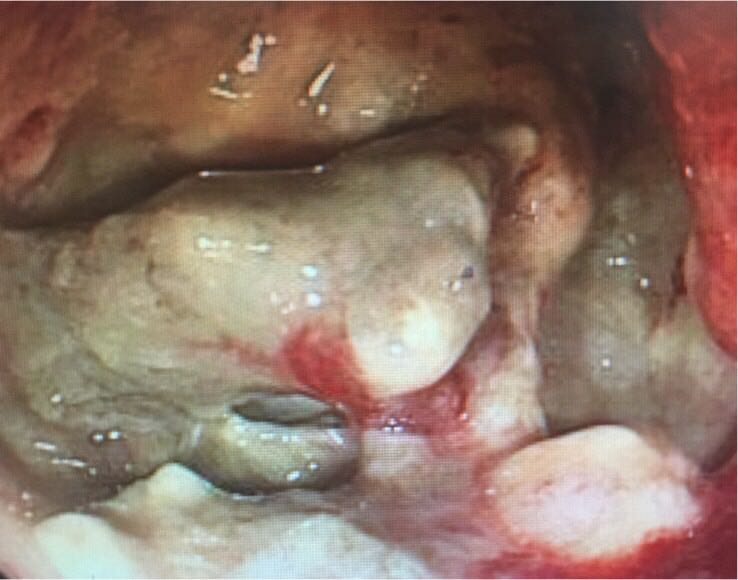

中年男性患者,主因腹胀伴大便不畅1月就诊,行肠镜见回盲部粪便堆积,清理后见回盲部偏心型肿物,表覆污秽,回盲部肠腔狭窄。右半结肠癌以肿块型占多数,左半以溃疡型居多,由此临床表现不同。